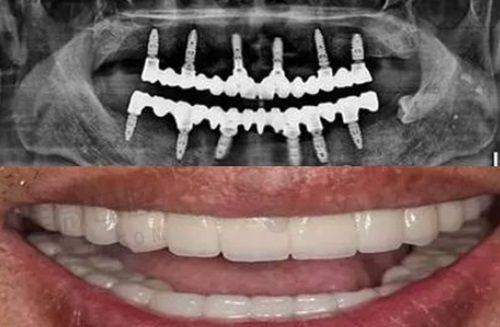

种植牙方面则采取国内外主流品牌材料,使用CBCT数字影像精细定位植体位置,全程操作由从业多年种植医生主导,多年来积累了良好的口碑。